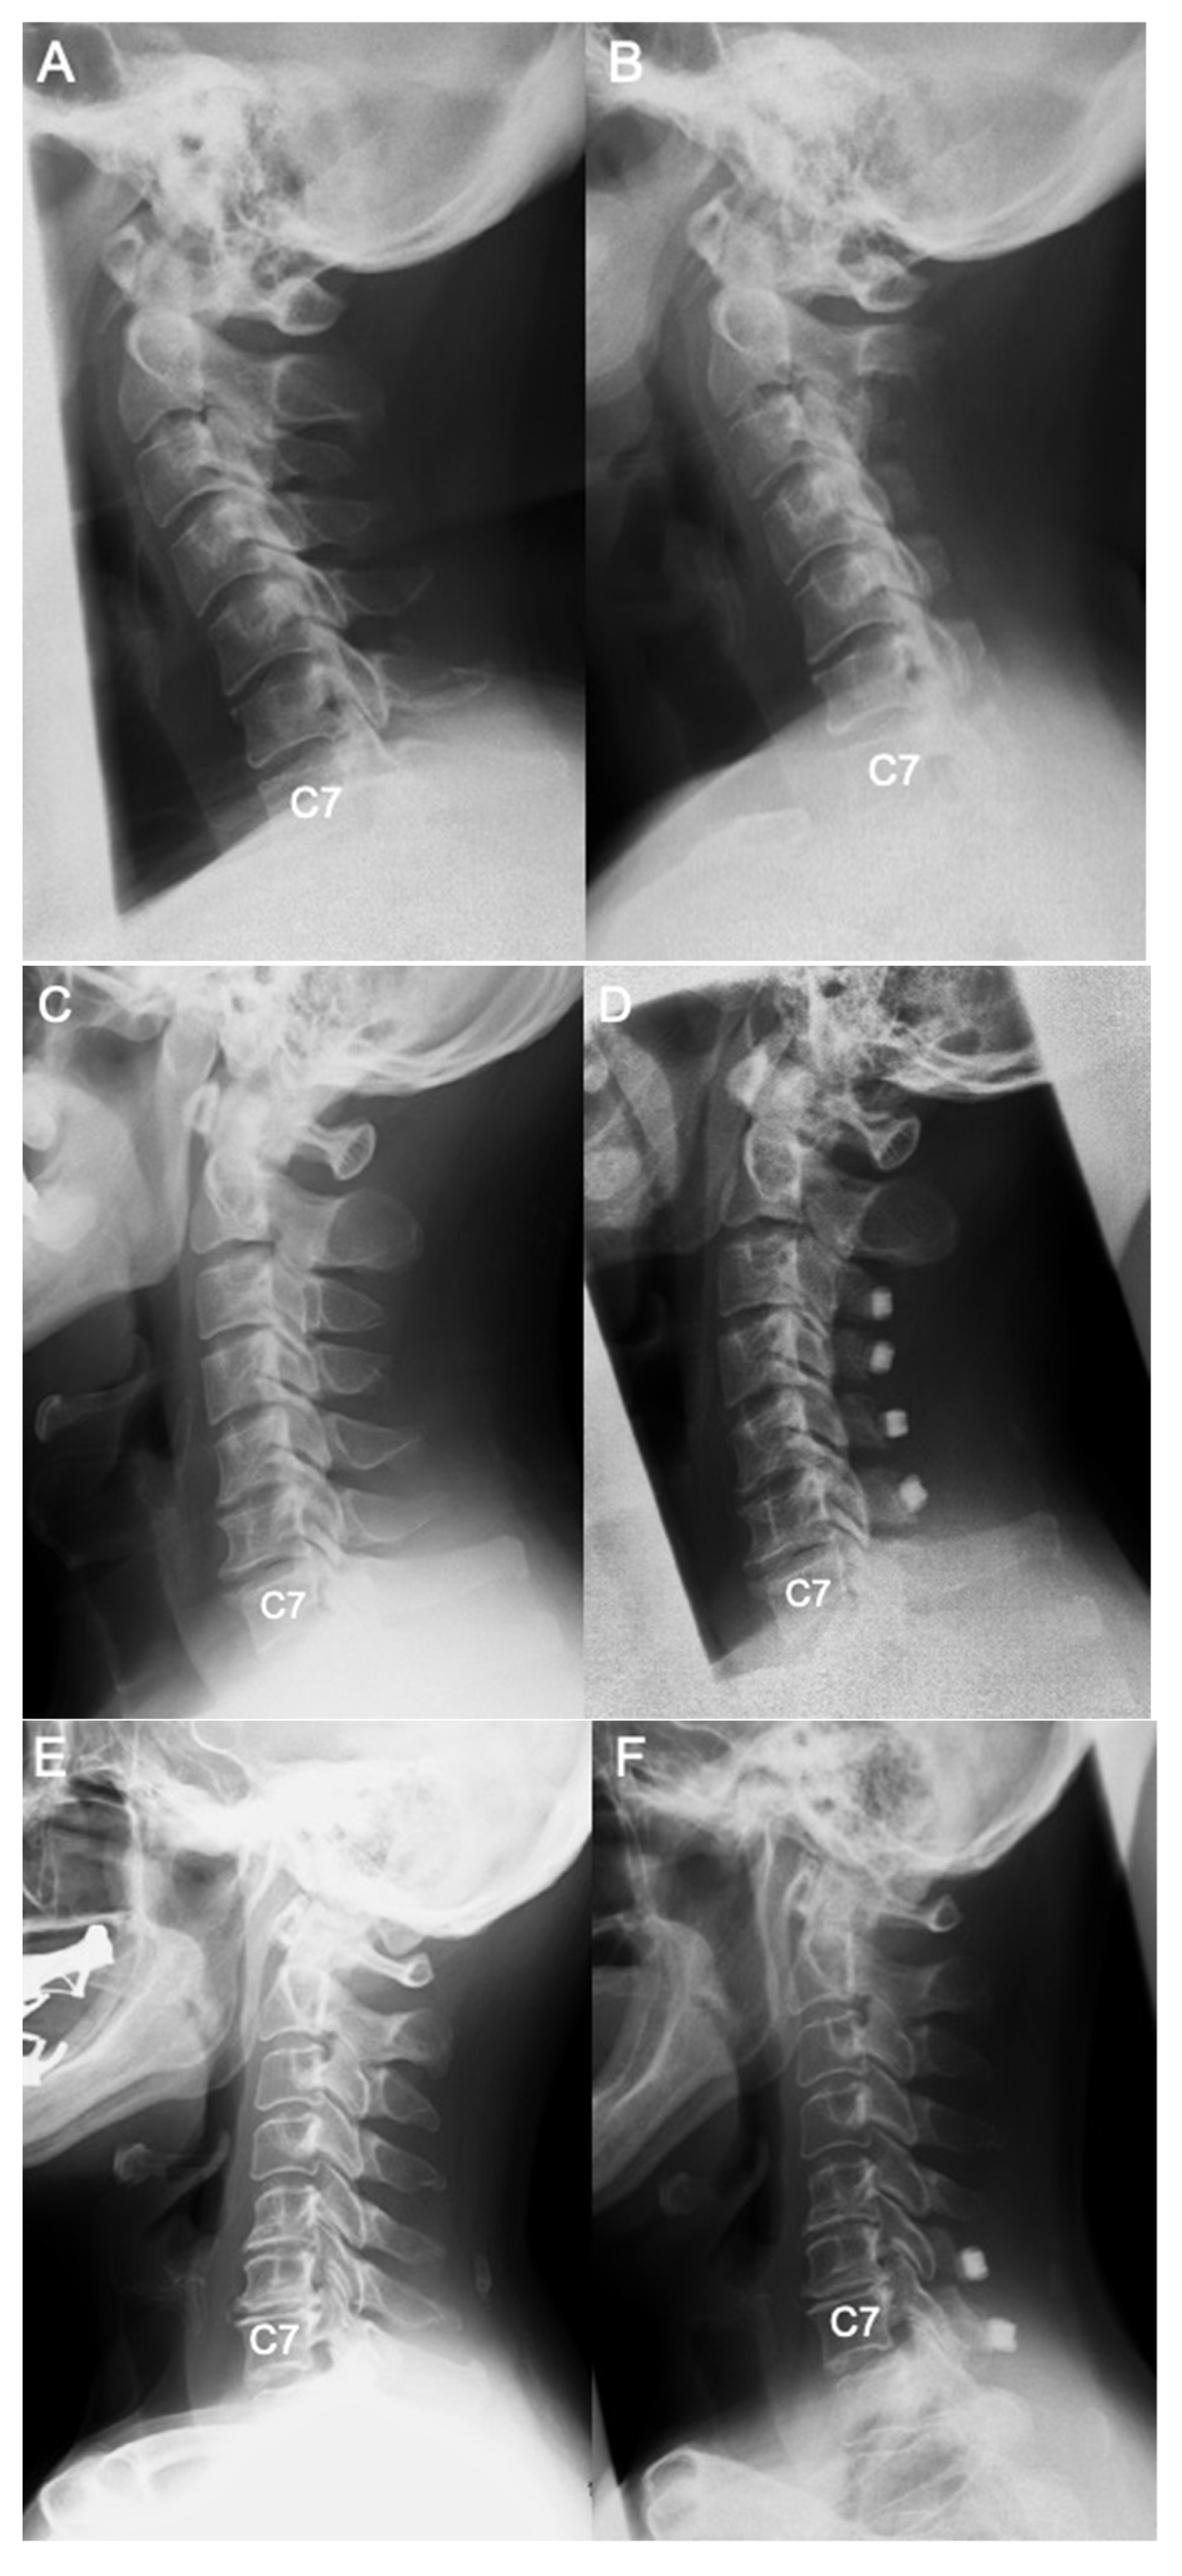

Differences in Demographic and Radiographic Characteristics between Patients with Visible and Invisible T1 Slopes on Lateral Cervical Radiographic Images

2.2. Radiological Assessment